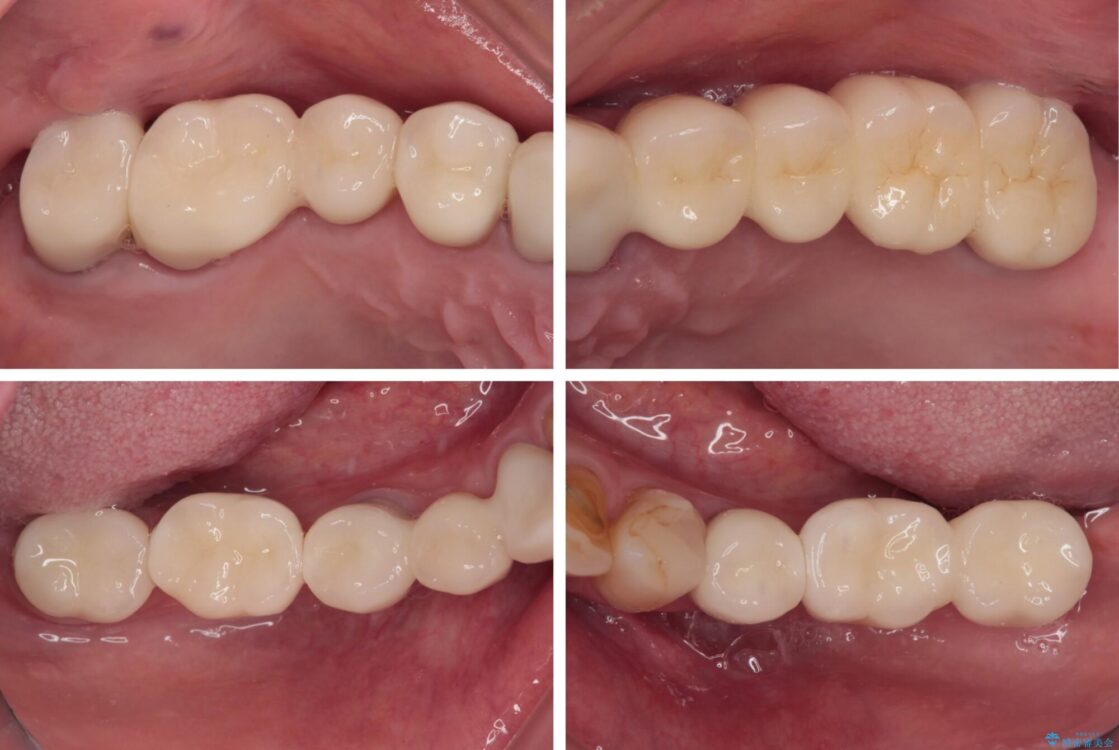

治療後

• 放置したインプラントとインビザライン 全顎リカバリー治療 治療後画像